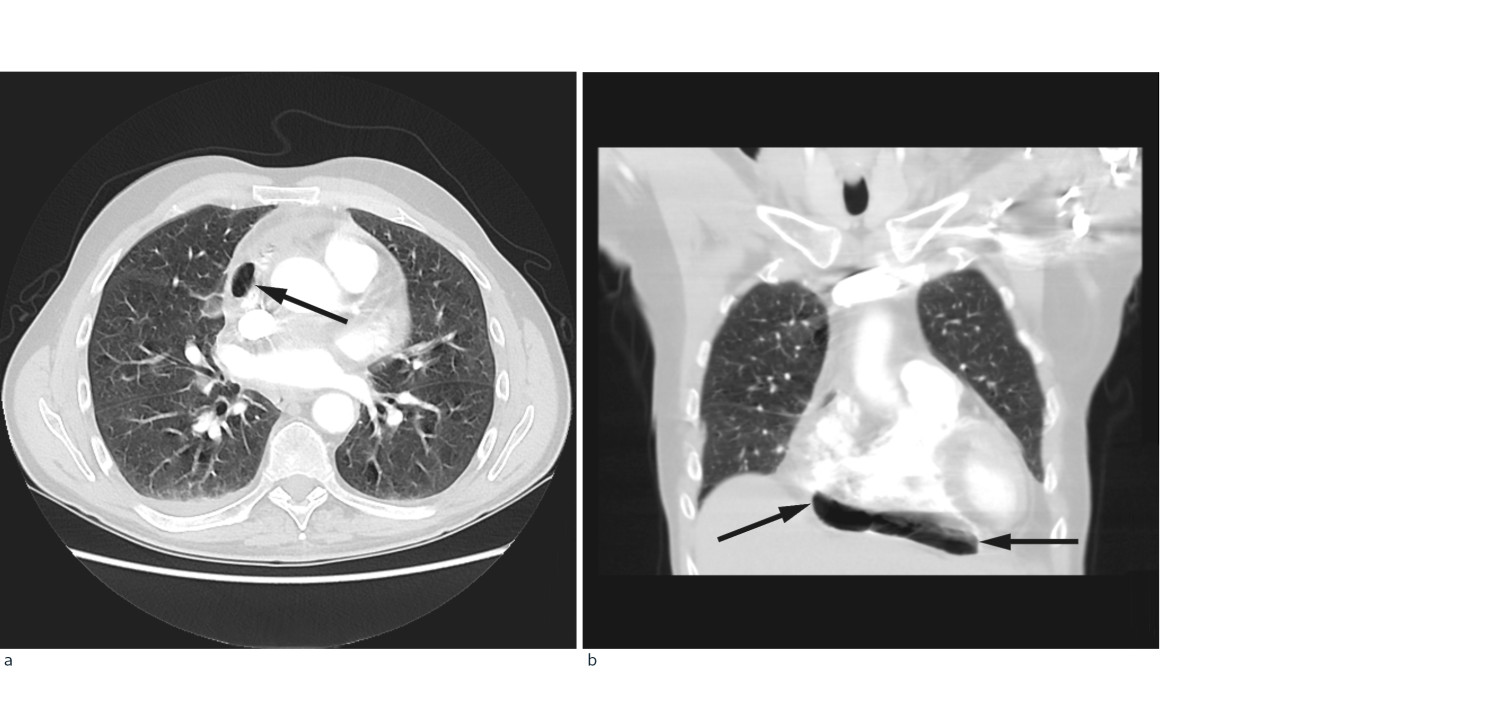

På mistanke om infeksjonsutvikling med utgangspunkt i lever/galleveier eller pancreas, ble intravenøs behandling med cefotaxim 1 g x 4 startet. Ultralyd abdomen viste slanke galleveier, men radiolog anbefalte CT abdomen for endelig avklaring. Dette ble utført samme dag supplert med CT thorax med lungeemboliserie. Underveis i denne undersøkelsen fikk pasienten akutt økende dyspné med metningsfall til 70 %, takypné med respirasjonsfrekvens på 22/minutt og takykardi med puls på 130 slag/minutt, ledsaget av kraftig forverring av smertene i høyre hemithorax. Onkolog og anestesilege ble tilkalt. Med ventilasjonsstøtte på maske klarte pasienten å gjennomføre undersøkelsen som viste fri luft i mediastinum, hovedsakelig i perikard, samt noe perikardeffusjon (fig 1). Lekkasjestedet kunne ikke påvises. I buken var det ingen fri luft.

Pneumomediastinum er definert som fri luft i mediastinum. Dette oppstår enten fordi alveoler sprekker eller fordi luft lekker fra respirasjons- eller gastrointestinalkanalen. Mediastinalt emfysem er oftest traumatisk betinget fra stumpt traume mot thorax eller iatrogent forårsaket, men kan også oppstå spontant (2). Luften kan bevege seg inn i perikardhulen, pneumoperikard, og forårsake perikardial tamponade. Ubehandlet kan dette være fatalt. Retrosternale brystsmerter som forverres ved inspirasjon og dyspné er vanlige symptomer på pneumoperikard. Ekkokardiografi kan bekrefte tilstanden og eventuell tamponade, og man kan utføre perikardiocentese for akutt avlastning. Dette gir også mulighet for biokjemisk analyse og histologi.

I foreliggende pasienthistorie var det spredning av både kreftceller og bakterier til epi- og perikard. Ved obduksjonen ble det ikke påvist økt luft/gass i perikard. Dette kan likevel ikke utelukkes, da man ikke spesifikt undersøkte for dette. Fistel mellom perikard/mediastinum og øvre gastrointestinalkanal eller trachea ble heller ikke avdekket, skjønt en liten åpning kan heller ikke utelukkes. På CT-undersøkelsen tatt dagen før dødsfallet er luft godt synlig (fig 1), men det var ikke mulig å identifisere lekkasjestedet. Sannsynligvis har maligne celler erodert perikard og epikard fra mediastinum, som ledd i det infiltrative vekstmønsteret, hvilket kan ha skapt en ventil for bakterier og luft. Fri luft/gass kunne også tenkes å ha oppstått som et (bi-)produkt av en bakteriell superinfeksjon med autolyse og vekselvirkning mellom bakterielt toksin og karsinomceller. Infeksjoner med gassproduserende bakterier i tarm eller bløtvev gir imidlertid som regel kun små gasslokulamenter på CT. Mikrobene som ble påvist er heller ikke typisk gassproduserende. Pasienten hadde ikke gjennomgått invasive prosedyrer utover biopsitakning fra lymfeknuter i øvre mediastinum, som ble utført tre uker tidligere. Denne prosedyren er rapportert å kunne forårsake penumomediastinum, men da som en akutt komplikasjon (5). Bruk av steroider og antibiotika i kombinasjon kunne potensielt forårsaket kolonisering eller infeksjon av sopp i oesophagus, med påfølgende ruptur. Det ble derimot ikke sett tegn til dette under obduksjonen. Pneumomediastinum kan utløses av kraftige hosteanfall, uten at en slik rift i luftveiene er synlig på CT. Iomeron, kontrastmidlet som gis i forbindelse med CT, kan utløse hoste, men dette er ikke journalført som et fremtredende symptom hos denne pasienten.

Retrospektivt burde bakteriell perikarditt ha vært vurdert som en differensialdiagnose i løpet av dette sykdomsforløpet. Diagnostikken ble derimot komplisert av malign sykdom og fravær av flere av de klassiske tegnene vi forbinder med denne tilstanden. Dette gjorde at bakteriell perikarditt ikke ble erkjent før obduksjonsrapporten forelå. Det er dog vanskelig å se for seg at infeksjonen i seg selv var dødelig. 100 ml puss er neppe tilstrekkelig til å forårsake tamponade, og pasienten var ikke septisk preget. Gassen i perikard truet imidlertid med tamponade, selv om det ikke var tegn til dette på CT-undersøkelsen tatt dagen før pasienten døde. Kompresjon av høyre ventrikkel kunne gi redusert slagvolum med fall i blodtrykk og takykardi, eventuelt rask atrieflimmer eller ventrikkelflimmer og sirkulatorisk kollaps. Ekko ville gitt diagnostisk avklaring, og perikardiocentese kunne ha drenert luften. Fordi vi ikke har ekko tilgjengelig på Radiumhospitalet, ville dette medført overflytting til intensivavdeling. Vi mener det kan diskuteres hvorvidt det ville vært riktig i denne situasjonen, gitt pasientens utbredte kreftsykdom og korte forventede levetid. Kasuistikken illustrerer viktigheten av bred differensialdiagnostisk tenkning ved uspesifikk symptomatologi hos pasienter med kreft. Disse pasientene har økt risiko for sjeldne og alvorlige infeksjoner og komplikasjoner. Kasuistikken belyser også en etisk problemstilling knyttet til behandling av pasienter med inkurabel kreftsykdom og kort forventet levetid: Når akutte komplikasjoner oppstår, hvor mye skal gjøres? Fordeler og ulemper ved eventuelle tiltak må vurderes nøye opp mot hverandre.